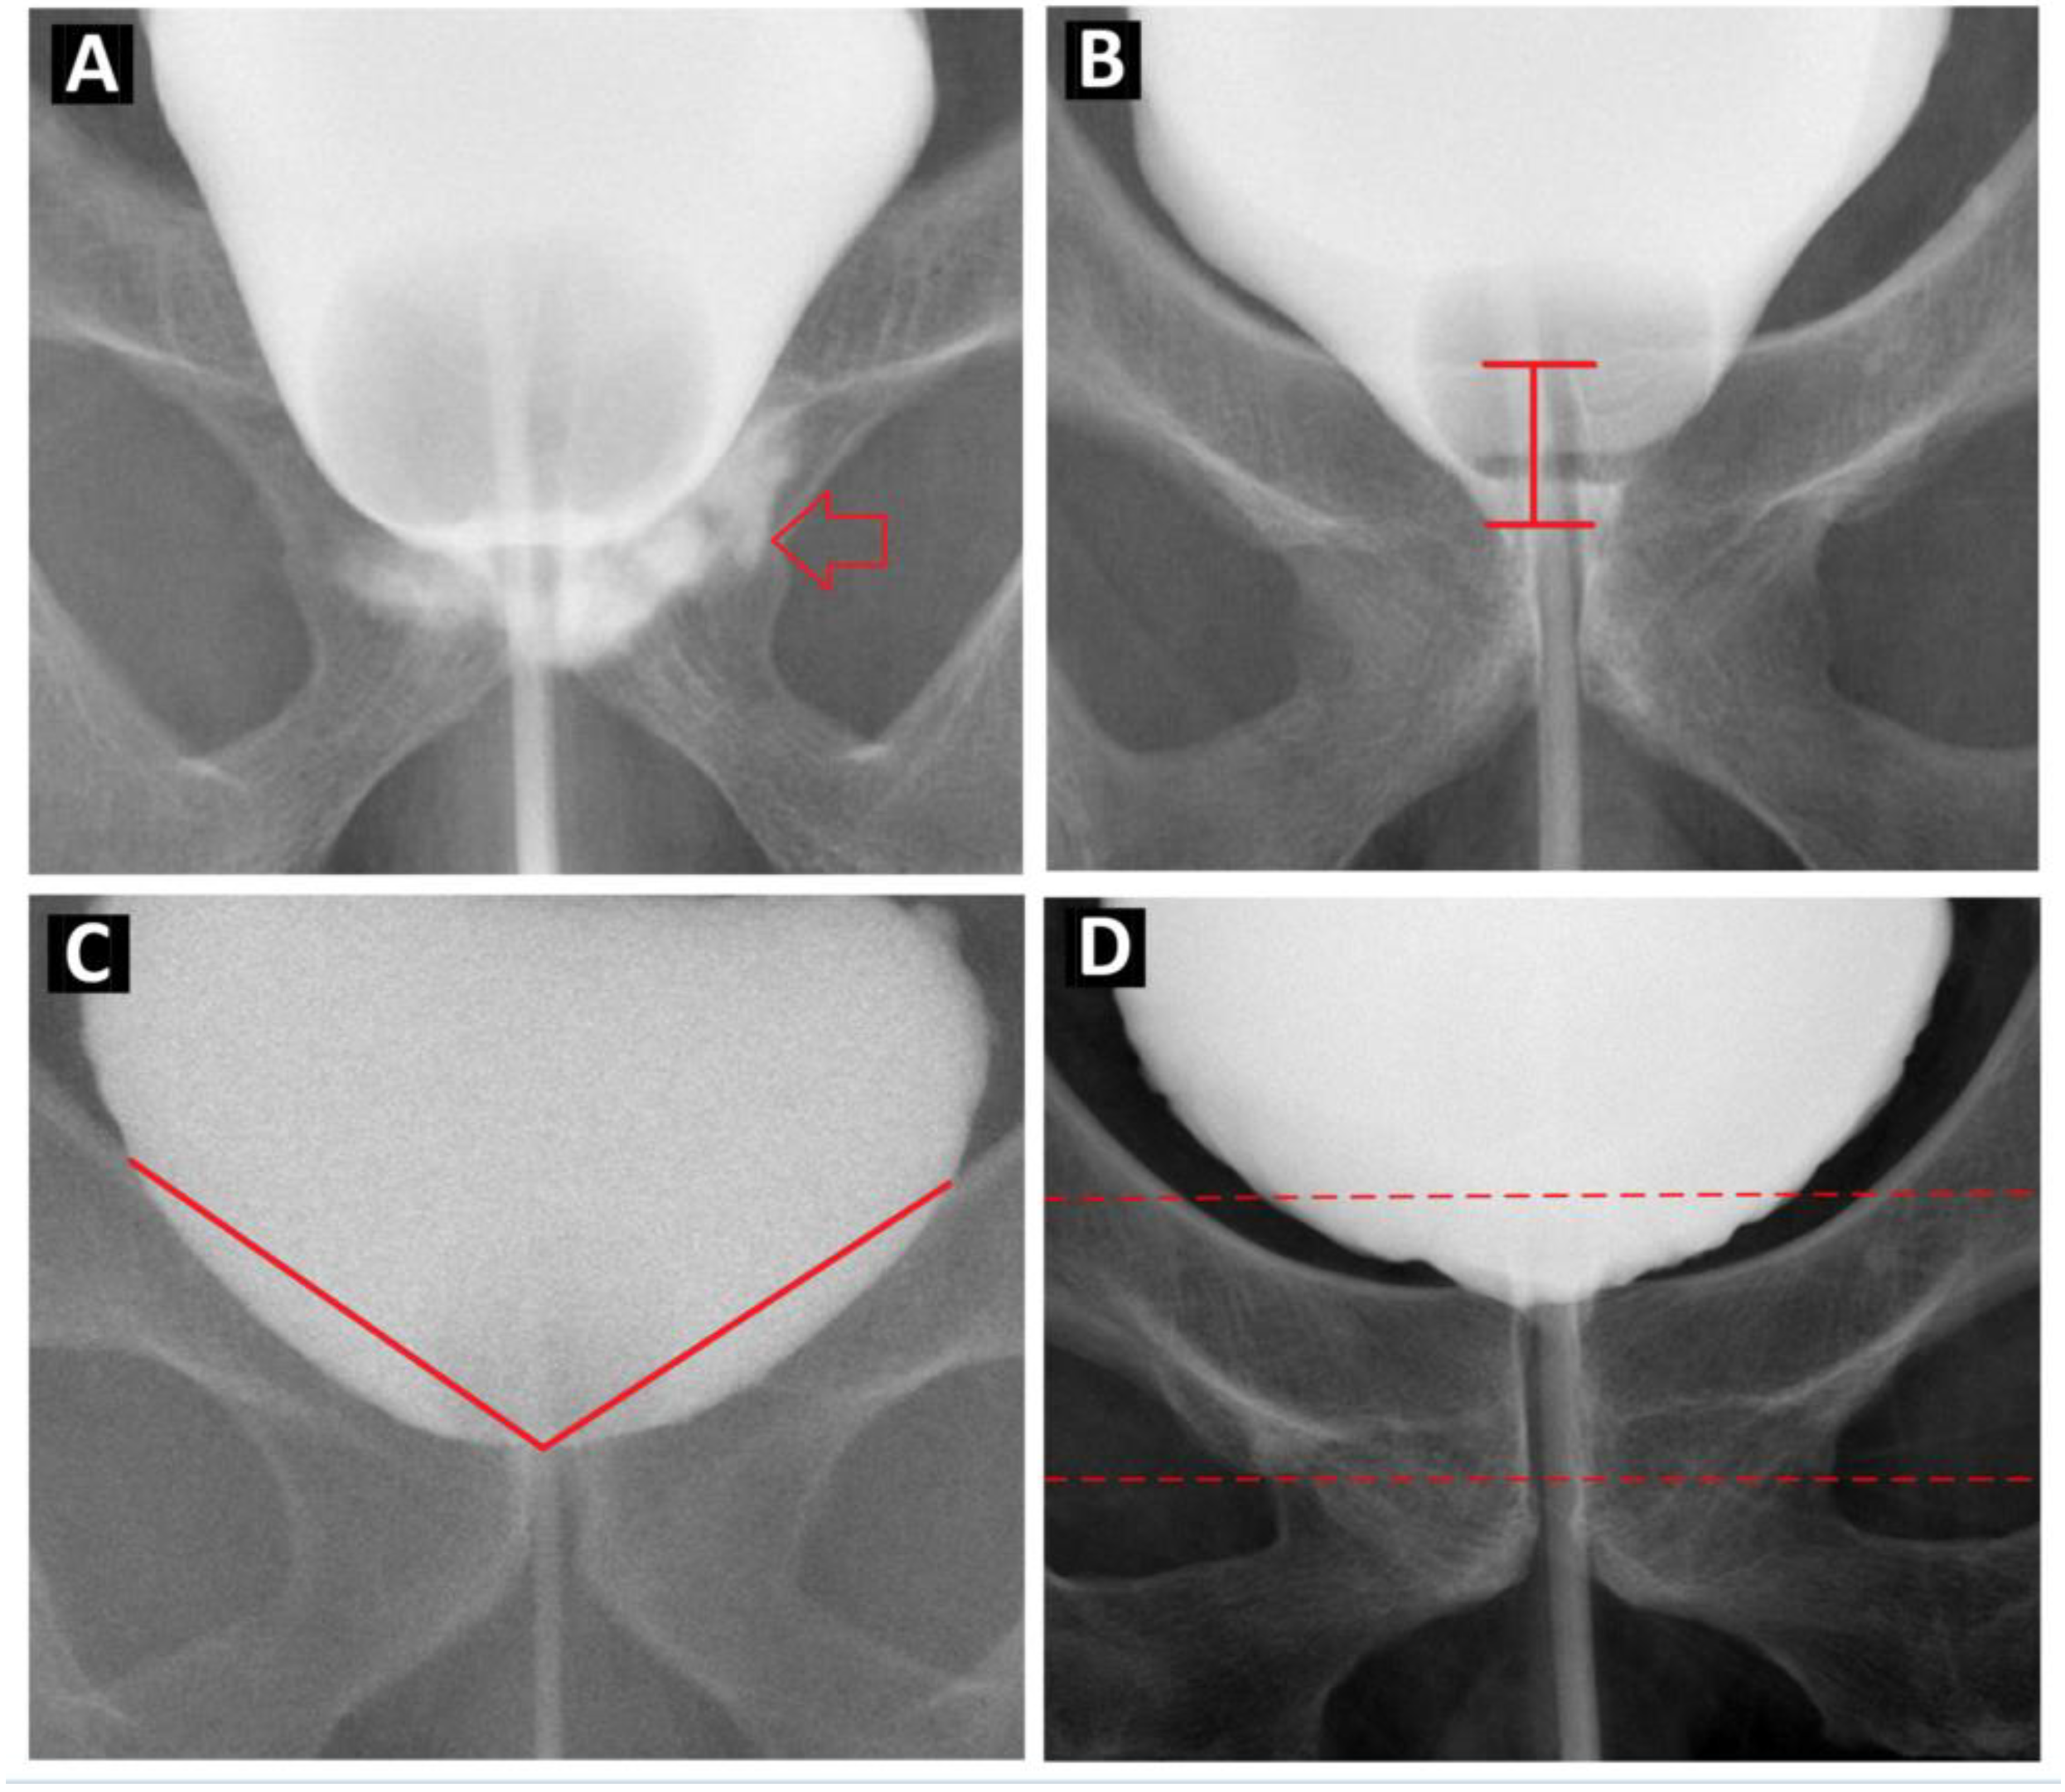

| Anastomosis site urine leakage (%) | * 0.011 | * 0.04 | ||

| Yes | 12 (14.8) | 29 (32.6) | ||

| No | 69 (85.2) | 60 (67.4) | ||

| Downward BN, cm (SD, range) | 0.74 (0.49, 0.1–3.5) | 1.31 (0.68, 0.1–3.5) | ** <0.001 | * 0.011 |

| BN angle, degree (SD, range) | 128.37 (18.0, 83.9–170.7) | 110.78 (20.2, 62.6–167.2) | ** <0.001 | 0.122 |